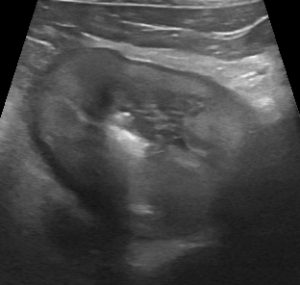

Longitudinal plane view of the bladder in a dog with presumed immune-mediated thrombocytopaenia and resulting haematuria.

The entire bladder wall has loss of normal layering and instead appears almost uniformly hyperechoic. The clot in the lumen is avascular on Doppler interrogation. This is a rather distinctive appearance. It’s important to say that these dogs may not necessarily have other physical signs of clotting disorders accompanying their lower urinary signs.